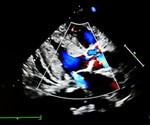

What is Mitral Regurgitation?